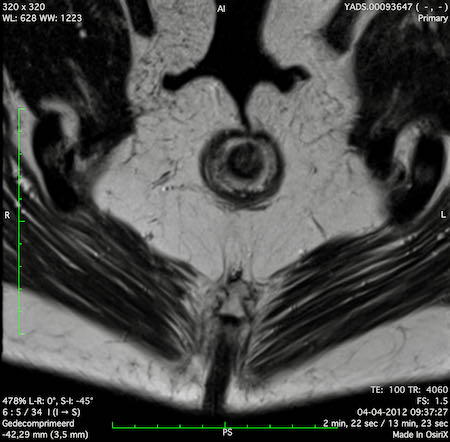

Hình ảnh

Các hình ảnh được cung cấp cho thấy ung thư biểu mô tế bào nhẫn với tình trạng dày lan tỏa thành trực tràng, hình ảnh bia bắn điển hình, và sự xâm lấn mỡ mạc treo trực tràng.